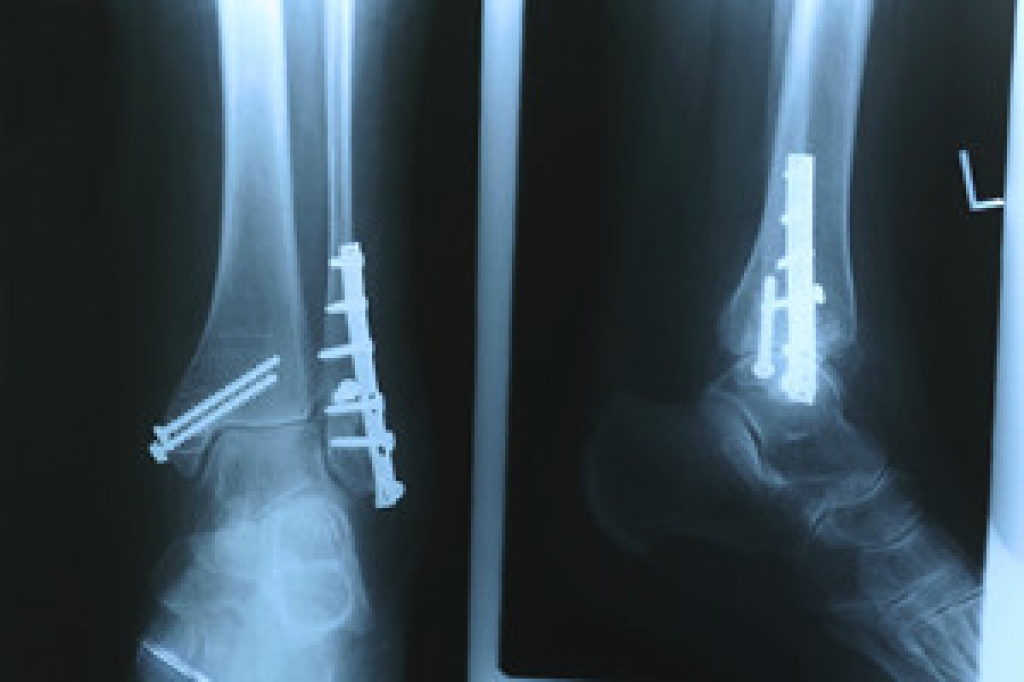

Treatment

Just as the range of causes varies widely, so do treatments. Some more common treatments are rest, ice packs, keeping pressure off the foot, orthotics and braces, medication for inflammation and pain, and surgery.